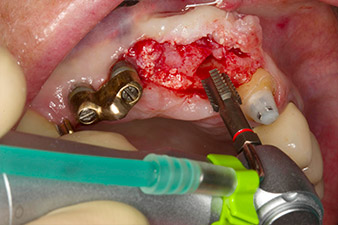

El hueso alveolar de la posición 22 resultó tener unas dimensiones suficientes. Las figuras 2 y 4 muestran la preparación del lecho del implante, el corte de rosca y la colocación del implante con el equipo Implantmed.

El nuevo motor para implantología se utilizó siempre con los contra-ángulos quirúrgicos adecuados de W&H.

Para compensar la pérdida de hueso periodontal y conseguir un resultado estético, el implante se combinó con una regeneración ósea guiada con material sustituto xenógeno y con una membrana de colágeno

(figuras 5 y 6).